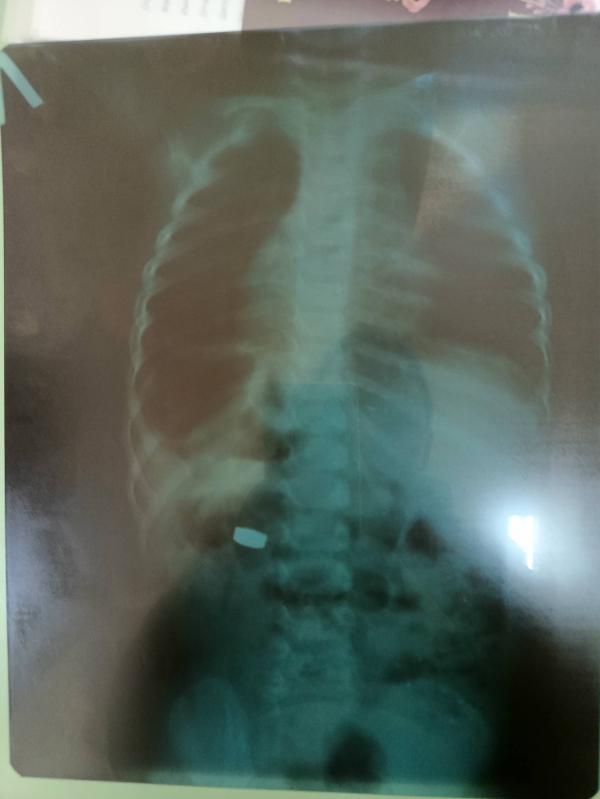

Ребенок проглотил батарейку: госпитализация, наблюдение и возможные последствия

Вечером проглотил батарейку, госпитализировали под наблюдение, утром вышла естественным путем, выписали.... Но врач сказал, что могут быть последствия, надо ждать результаты анализов